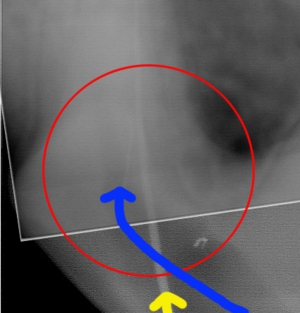

かなり削りましたが、この状態で初めて破折ファイルを目視することが可能となります。レントゲンではわかりやすいのですが、およそ0.5~0.8mmを見ることが可能です。

少しづつ超音波などで周辺を掘削しファイルを動揺させます。

無事に摘出し新たなファイルを入れた状態です。

それでは今回入れたファイルと以前ファイルを入れられた状態の角度を比較するために画像を重ねて表示してみましょう。

正しくファイルを入れた方向と最初にファイルを破折させた角度を見ると、折れたファイルはかなじ前方から根管口に入っていることがわかります。このような現象は、最初に根管へアクセスする際、歯をあまり削らずに行おうとしたために、急角度にファイルが曲がって根管口へ突入したために破折したことがわかります。下記に示すように、青でファイルを挿入すると折れますが、黄色の位置から挿入すると折れることはありません。根管に対してできる限りまっすぐにいれることのできるアクセスを行うことが重要です。